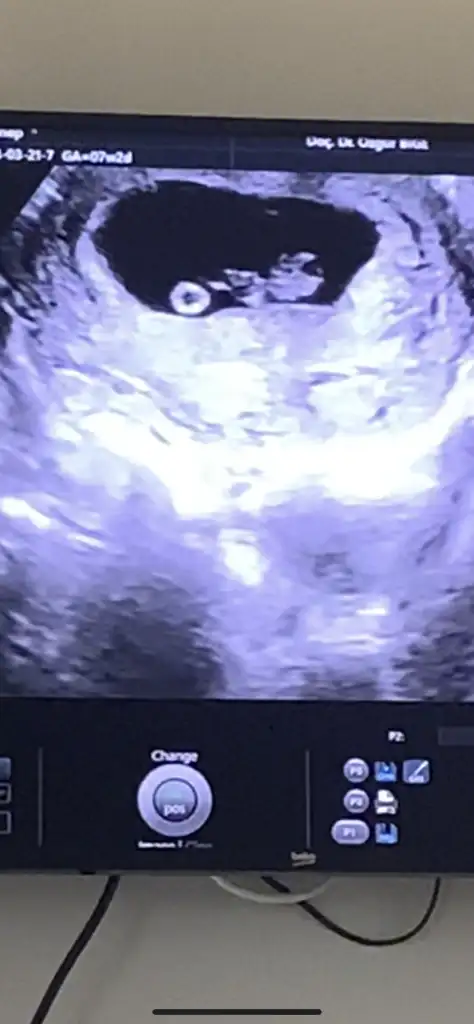

Cinsiyet tahmini yapabilen varmı

Benimkine de bakar mısınız 😊 10+2